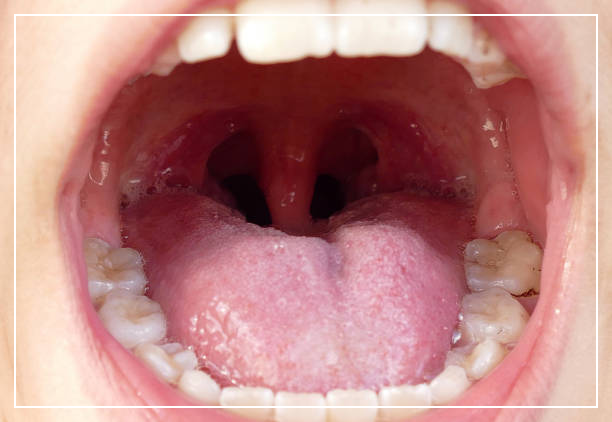

많은 사람들이 입 속에서 노란색의 작은 입자가 발생하는 상황을 겪어봤을 것입니다.

이 미세한 입자는 편도결석이라고 부르며, 편도에 있는 미세한 구멍들에 음식물 잔여물과 세균이 축적되어 결석이 형성되는 현상입니다.

편도결석은 편도에 형성된 작은 석회질 결정으로, 일종의 표면 결속물질이라고 할 수 있습니다.

편도는 인두와 입천장 사이에 위치한 조직이며, 식도와 마찬가지로 소화와 호흡 과정에 관여하는 중요한 역할을 합니다. 편도결석은 편도 내부에 쌓인 석회질이 결정화되어 형성되는데, 이로 인해 편도에 장애가 발생할 수 있습니다.